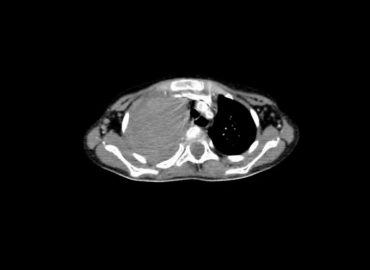

Paciente masculino de 47 años, cursando infección por SARS CoV-2, presenta afasia mixta y disartria